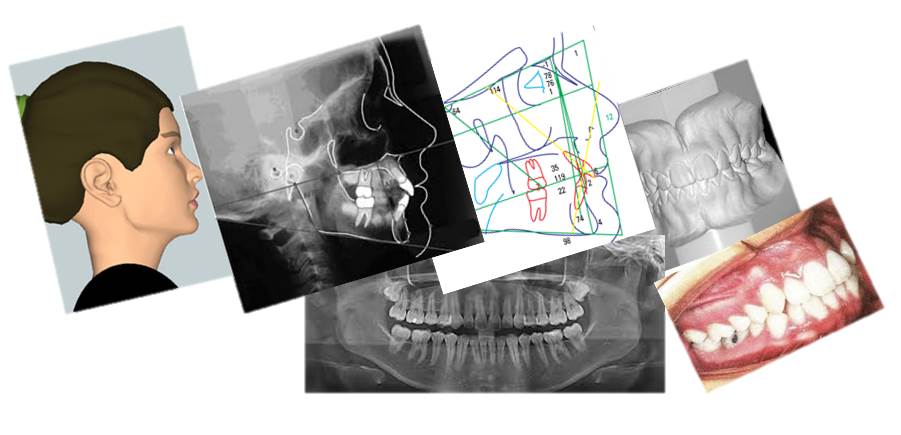

Os exames mais comuns incluem radiografia panorâmica, telerradiografia lateral, fotografias intra e extrabucais, escaneamento intraoral ou modelos digitais da arcada dentária, além da análise cefalométrica.

A versão digital oferece imagens mais nítidas, maior precisão nos traçados cefalométricos e fácil compartilhamento com softwares ortodônticos, agilizando o planejamento e acompanhamento do tratamento.